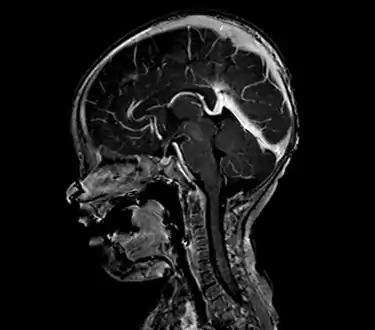

Large arteriovenous malformation of the parietal lobe

An AVM diagnosis is established by neuroimaging studies after a complete neurological and physical examination.[5][11] Three main techniques are used to visualize the brain and search for AVM: computed tomography (CT), magnetic resonance imaging (MRI), and cerebral angiography.[11] A CT scan of the head is usually performed first when the subject is symptomatic. It can suggest the approximate site of the bleed.[3] MRI is more sensitive than CT in the diagnosis of AVMs and provides better information about the exact location of the malformation.[11] More detailed pictures of the tangle of blood vessels that compose an AVM can be obtained by using radioactive agents injected into the blood stream. If a CT is used in conjunctiangiogram, this is called a computerized tomography angiogram; while, if MRI is used it is called magnetic resonance angiogram.[3][11] The best images of an AVM are obtained through cerebral angiography. This procedure involves using a catheter, threaded through an artery up to the head, to deliver a contrast agent into the AVM. As the contrast agent flows through the AVM structure, a sequence of X-ray images are obtained.[11]